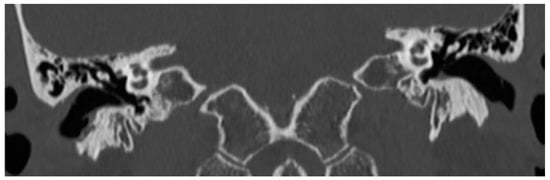

3.1. Patient 1

3.2. Patient 2

3.3. Patient 3